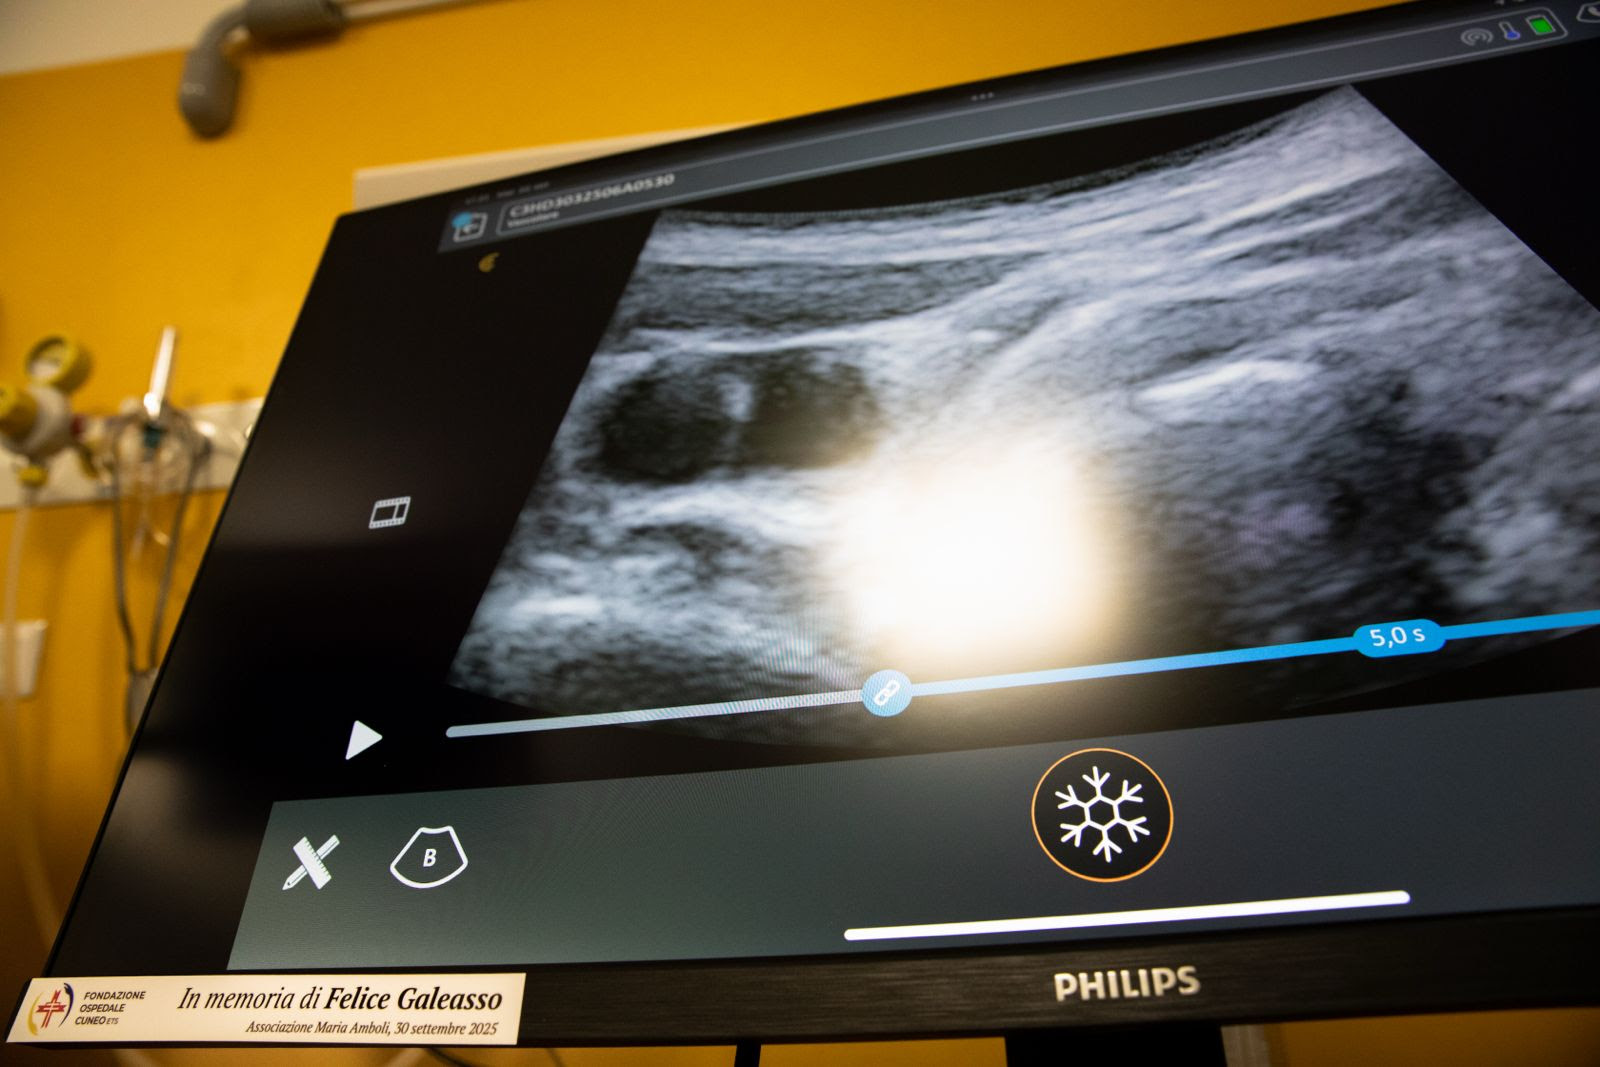

A beneficio del Pronto Soccorso sono stati invece donati quattro ecografi palmari per la Shock Room con i relativi monitor. La donazione è stata resa possibile grazie al contributo dell’Associazione Maria Amboli, costituita nel 2014 da Felice Galeasso. A nome dell’Associazione, Valeria Belliardi ha dichiarato di aver voluto, con questa donazione, dare seguito al desiderio di Felice, recentemente scomparso, di contribuire ai progetti della Fondazione Ospedale Cuneo. Gli ecografi palmari sono dispositivi compatti che permettono di effettuare ecografie in situazioni di emergenza, riducendo il tempo tra diagnosi e intervento. Il progetto consente di migliorare sensibilmente l’approccio tempestivo e in équipe multiprofessionale e multidisciplinare al paziente critico aumentando l’efficienza e la sicurezza delle cure, migliorando gli esiti. La visione contemporanea delle immagini ecografiche da parte di tutta l’équipe consente inoltre la rapida condivisione delle informazioni.